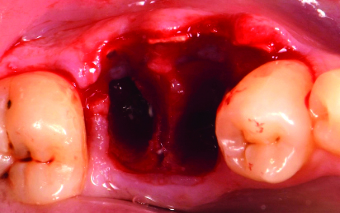

Volumetric restoration using an equine-derived Flex Cortical Sheet.

The clinical case concerns a 44-year-old patient who had a root remnant of element 46, which was not recoverable. The preoperative CBCT showed a sufficient amount of bone in the vertical direction but with a very thin vestibular cortical and a high risk of resorption. These conditions represented the correct clinical indication for the use of the Modified Periosteal Inhibition technique. To protect the vestibular cortical layer, a 0.5-mm vestibularly bagged Flex Cortical Sheet was inserted between the alveolar bone and periosteum after hydration for 5-6 seconds with sterile saline solution. The presence of the flexible cortical sheet prevents the passage of pre-osteoclasts from the periosteum to the vestibular cortical, thus preventing their differentiation into mature osteoclasts. CBCT performed 4 months after surgery showed perfect maintenance of the original bone volumes and good mineralisation of the alveolus. At 7 months the definitive prosthesis was delivered to the patient’s satisfaction with the excellent aesthetic result achieved.